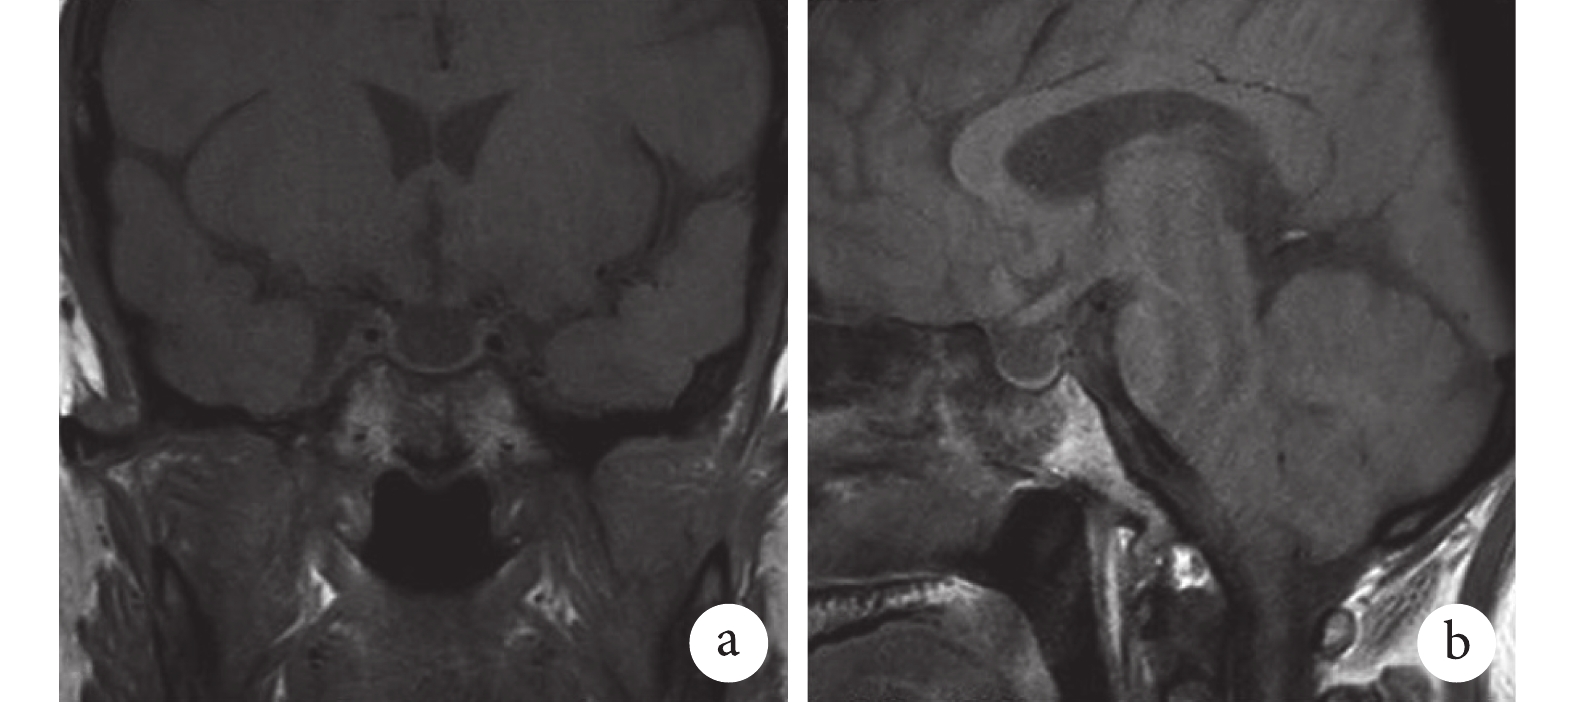

示鞍內空虛,垂體組織明顯變扁并緊貼于鞍底,鞍內大部分成腦脊液樣信號。

入院后完善各項輔助檢查:動脈血氣分析(未吸氧狀態下)示:pH 7.48,二氧化碳分壓 32 mm Hg,氧分壓 78 mm Hg,乳酸 0.5 mmo/L,實際碳酸氫根離子濃度 23.8 mmol/L,堿剩余 0.9 mmol/L。血常規示白細胞總數及各分類計數正常,紅細胞計數及血紅蛋白含量正常,血小板計數 95×109/L。肝功能、腎功能、心肌酶及離子均處正常水平。尿常規示白細胞 15 個/HPF,紅細胞 3 個/HPF,上皮細胞 4 個/HPF。便常規無異常。血淀粉酶、脂肪酶及尿淀粉酶均正常。甲狀腺功能示游離甲狀腺素、游離三碘甲腺原氨酸及總三碘甲腺原氨酸均處正常范圍低限值,促甲狀腺素水平正常。垂體功能五項測定示生長激素及促卵泡刺激素水平下降。降鈣素原與真菌 D 葡聚糖處正常范圍。呼吸道病毒免疫球蛋白(immunoglobin,Ig)M 抗體系列、支原體 IgM、衣原體 IgM 及軍團菌尿抗原均陰性。結核感染 T 細胞檢測陰性。腫瘤標志物全套未見明顯異常。C 反應蛋白 66.9 mg/L。紅細胞沉降率 26 mm/1 h。IgG、IgM、IgA、補體 C3、補體 C4均未見異常。類風濕組合、血管炎組合、血清 λ 輕鏈與 κ 輕鏈均無異常。抗核抗體譜示抗核抗體滴度 1∶100,JO-1 抗體陽性++,進一步行肌炎抗體譜測定,各項結果均正常。肺功能檢查提示限制性通氣功能障礙,彌散功能輕度障礙,一氧化碳彌散量 72%。心電圖提示竇性心律、正常心電圖。心臟彩色多普勒超聲成像示心內結構及功能未見異常。全腹平掃及增強 CT 提示胰腺周圍廣泛滲出,脂肪間隙模糊不清,腸系膜上動脈周圍見軟組織影環繞,部分腸管周圍及腸系膜走形區內見軟組織密度影,腹主動脈形態欠規整、壁增厚,雙腎周軟組織浸潤影,雙側腎盂擴張積水,增強掃描未見強化,脾臟體積大,密度均勻,增強掃描未見異常強化,腹盆部多發骨質改變(圖3)。全身骨顯像提示右側肩胛骨、雙側部分前肋、部分胸椎椎體、雙側髂骨、雙側髖臼、雙側肱骨、雙側股骨、雙側脛腓骨及左側踝關節多發斑片狀高密度及高、低混雜密度骨質破壞影,伴放射性攝取增強(圖4)。垂體磁共振成像(magnetic resonance imaging,MRI)平掃提示鞍內空虛,垂體組織明顯變扁并緊貼于鞍底,鞍內大部分成腦脊液樣信號(圖5)。于右側股骨遠端內側病灶處行骨組織活檢,病理學及免疫組織化學分析示骨小梁間見有纖維組織增生,有大量組織細胞、泡沫細胞浸潤,并見嗜酸性粒細胞,未見朗格漢斯細胞增生,CD68(+),CD163(+),S-100少許(+),Ki67個別(+),CD1a(–),CD207(–),CD10(–),CK(AE1/AE3)–,SATB2(–),CD56(–)(圖6)。診斷:埃德海姆–切斯特病(Erdheim-Chester disease,ECD)。患者因經濟條件有限未行 BRAF 突變檢測,予重組人干擾素 α-2a(interferon α-2a,IFNα-2a)300 萬 IU 隔日 1 次皮下注射。